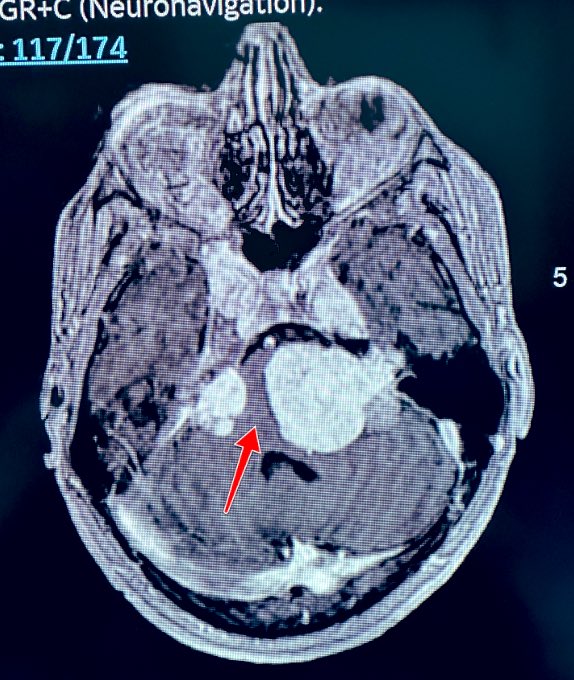

2️⃣جميعهم اعتذر عن اجراء العملية لخطورتها على حياته

براك وصل لمرحة لا يستطيع الوقوف ولا البلع وبالكاد يتنفس

قالوا لوالده:خذ ابنك ليتوفى بين أسرته وأحبته!

بعد أسبوعين من اجراء العملية في @HMG بريدة

براك يتماثل تدريجيا للشفاء بفضل الله